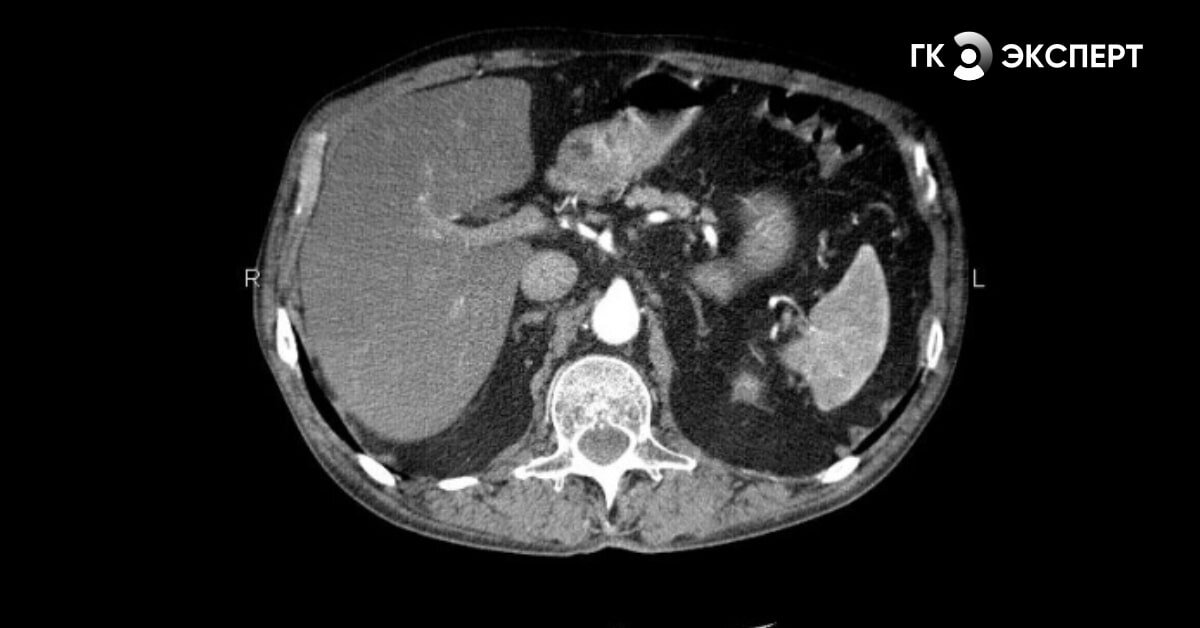

— Что показывает МСКТ желудка?

— КТ (МСКТ) желудка помогает выявить такие патологии, как воспалительные изменения стенок желудка, язвенные поражения, аномалии развития, доброкачественные и злокачественные образования, наличие отдалённых метастазов.

Наверное, здесь стоит пояснить, что имеется в виду под отдалёнными метастазами. Скажем, врач исследует первичный злокачественный процесс в желудке. При сканировании он видит рядом расположенные органы, в которых и может обнаружить метастазы (например, в печени, лимфоузлах).